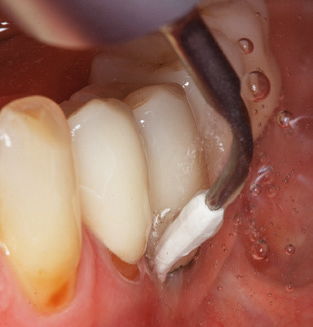

Of course, working tips for the cleaning of implant surfaces are also indispensable for SPT in patients fitted with implants. The implant cleaning attachment on the system used here is characterised by its tapered, hexagonal design. This design allows light, atraumatic penetration of the peri-implant pocket and displays a good cleaning performance (Fig. 7).

Following machine cleaning of the tooth and implant surfaces, the surfaces of the natural teeth are cleaned manually using standard hand instruments. When performing manual cleaning, particular attention must be given to maintaining the correct angle of application, appropriate sharpness, good support and working with the curette from apical to coronal. Either titanium or carbon curettes should be used for post-cleaning of the implant structures (Fig. 8). In addition to the use of ultrasonic devices, power jet devices can also be used in conservative dentistry. However, it must be taken into consideration that these procedures are not suitable for removing hard deposits and thus they cannot replace the use of hand instruments and ultrasonic instruments completely. In all cases, cleaning is followed by mechanical polishing of the accessible tooth and implant surfaces with polishing cups and polishing compounds (Fig. 9).